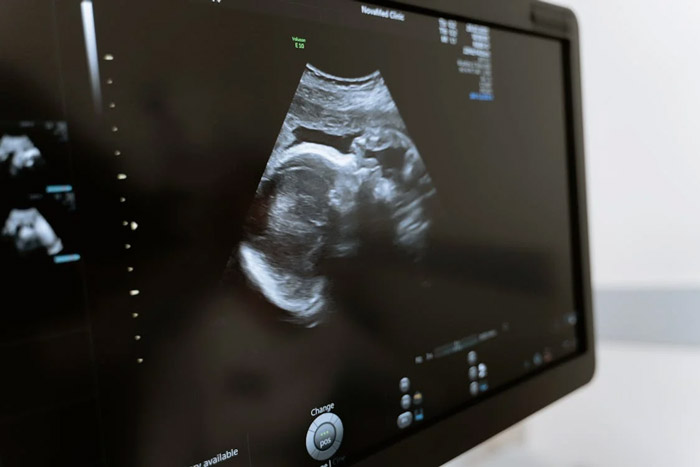

很多准妈妈在怀孕期间都会特别关注自身和胎儿的健康。不少准妈妈因一时疏忽,只重视常规的检查,却没及时做孕前基因检测,及早发现问题,最终生的娃出现染色体异常,为此后悔不早知道!

生育一个有严重单基因遗传病的患儿将会给其家庭以及社会带来极大的负担。大多数单基因遗传病具有致死、致畸或致残,仅5%有针对性的治疗手段且治疗非常昂贵,普通家庭根本难以承受。更令人惋惜的是,单基因病在胎儿发育期一般不会有结构畸形,因此像B超检查等常规孕产检往往难以准确排查胎儿患单基因遗传病的风险。